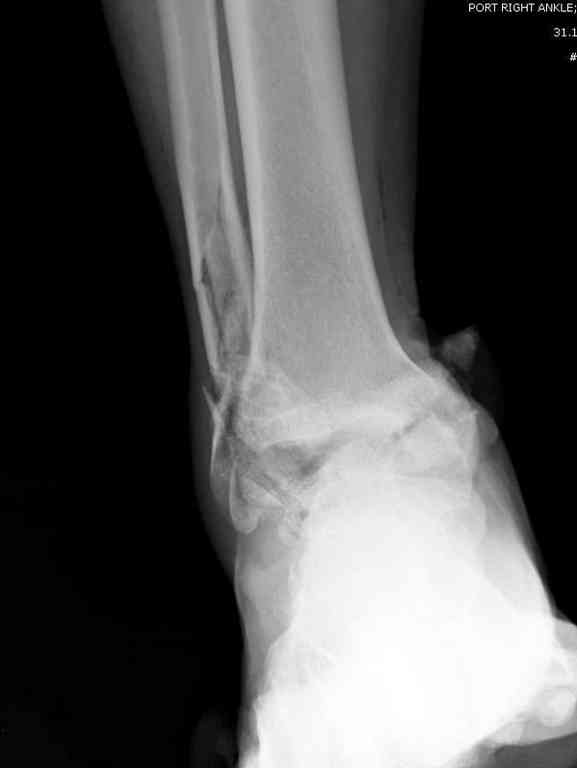

Прошу коллег помочь советом.3 дня назад поступила пациентка 23 года с переломом шейки ладьевидной справа, переломом лодыжек и заднего края б/берцовой кости со смещением и подвывихом кзади, переломом внутреннего мыщелка правого бедра без смещения. Дежурными хирургами проведена репозиция в левом г/ст суставе успешная, попытка репозиции таранной кости ухудшило положение отломков. Планируем провести повторную репозицию и фиксацию винтами. 1. Закрытая репозиция рентгенконтоль интраоперационный (аппарат Арман) ификсация из заднее-наружного доступа. 2. При неудачной закрытой репозиции переходим на открытое вправление двумя доступами медиальным и латеральным "по ходу оси таранной кости" и через дополнительный задний доступ вводим винты кортикальные 4,5 мм или 3,5 мм 3. после открытой репозиции фиксация двумя винтами через боковые доступы погружая их под суставную поверхность Сергей Зырянов ЦРБ Новосибирская область

z> 3 дня назад поступила пациентка 23 года с переломом шейки ладьевидной

z> справа, переломом лодыжек заднего края б/берцовой кости со смещением и

z> подвывихом кзади, переломом внутреннего мыщелка правого бедра без смещения.

Это на той же ноге, где таран, или нет? Если нет, эти сведения вряд ли влияют на планирование в отношении обсуждаемой таранной кости.

z> Планируем провести повторную репозицию и фиксацию винтами.

Есть смысл подумать не только о репозиции и остеосинтезе тарана (попытка сделать это закрыто без ЭОП, по-моему, неоправдана), но и об артродезе подтаранного сустава. Он поврежден уже, т.е. ожидаем артроз. Плюс кровоснабжение аваскулярного блока таранной кости будет

обеспечиваться со стороны пятки. Это ускорит реваскуяризацию блока тарана. Достаточно одного наружного доступа.

Уважаемый Сергей

В данном случае вероятность аваскулярного некроза очень высока, но пациентка молодая и нельзя лишать её шанса на сращение перелома. Нет ни

какого сомнения что необходимо выполнить открытую репозицию. Для выполнения качественной репозиции необходим визуальный контроль, ЭОП не достаточно.

Обычно используется доступ с остетомией внутренней лодыжки, но у вашей пациентки есть перелом лодыжки что можно использовать для доступа к таранной кости и в конце операции зафиксировать перелом лодыжки. К сожалению нет

переднезаднего снимка, так что через какую лодыжку идти не могу сказать.

Канулированные винты могут вам очень помочь.